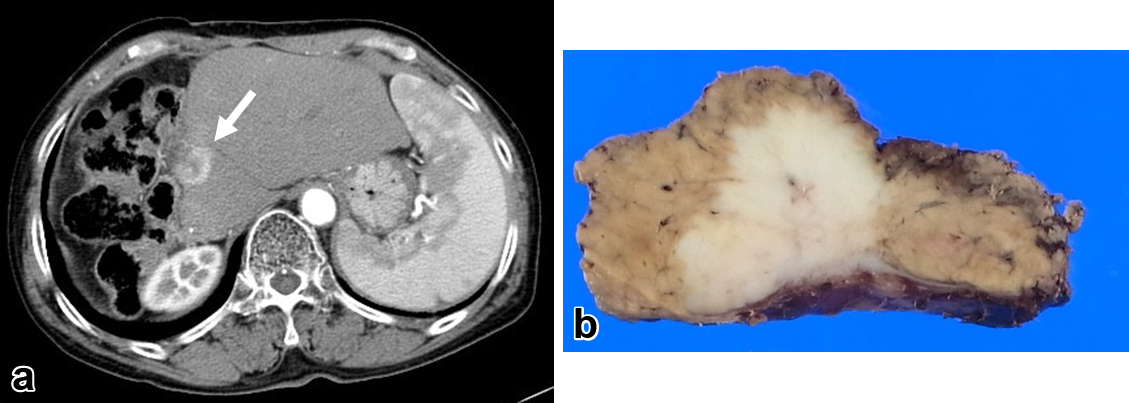

臨床経過(2):初回術後2年1か月,造影CTにて残肝のS1に2 cm大の腫瘤を認めた(Fig. 2a).腫瘤は辺縁に造影効果を認め内部造影は不良であった.ICC術後肝内再発が第一に疑われ,全身状態に問題がなく,肝外病変を認めなかったことから手術適応と判断した.手術は腫瘍を含めた肝S1部分切除術を施行した(Fig. 2b).腫瘍は肝S1表在であったが,肝実質側では腫瘍から1 cm以上のマージンをとって切除した.病理組織学的に切除した腫瘍は2 cm大の中分化型腺癌で脈管侵襲は認めず,切除断端は癌陰性であった.術後は患者の希望により化学療法は導入しなかった.

a) 2 years and 1 month after the initial operation, follow-up abdominal contrast CT revealed a mass of 2 cm in segment 1 of the liver (arrow). b) Macroscopic view of the resected specimen in the second operation showing a white solid tumor of 2 cm in size.